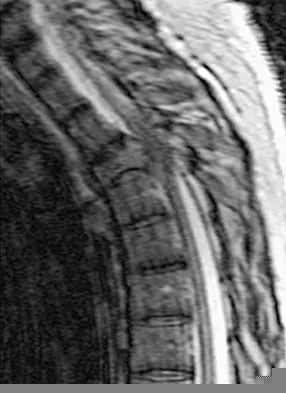

Question 6

A 19-year-old man has had back pain with activity, especially running in soccer and baseball, for the past 4 months. He denies any history of trauma. Examination reveals no motor weakness or sensory changes in the lower extremities. Range of motion shows increased pain with extension and mild limitation with flexion. A sitting straight leg raising test is limited at approximately 60 degrees bilaterally by back and buttocks pain. Plain radiographs are normal. MRI scans are shown in Figures 13a through 13e. What is the most likely diagnosis?

Explanation